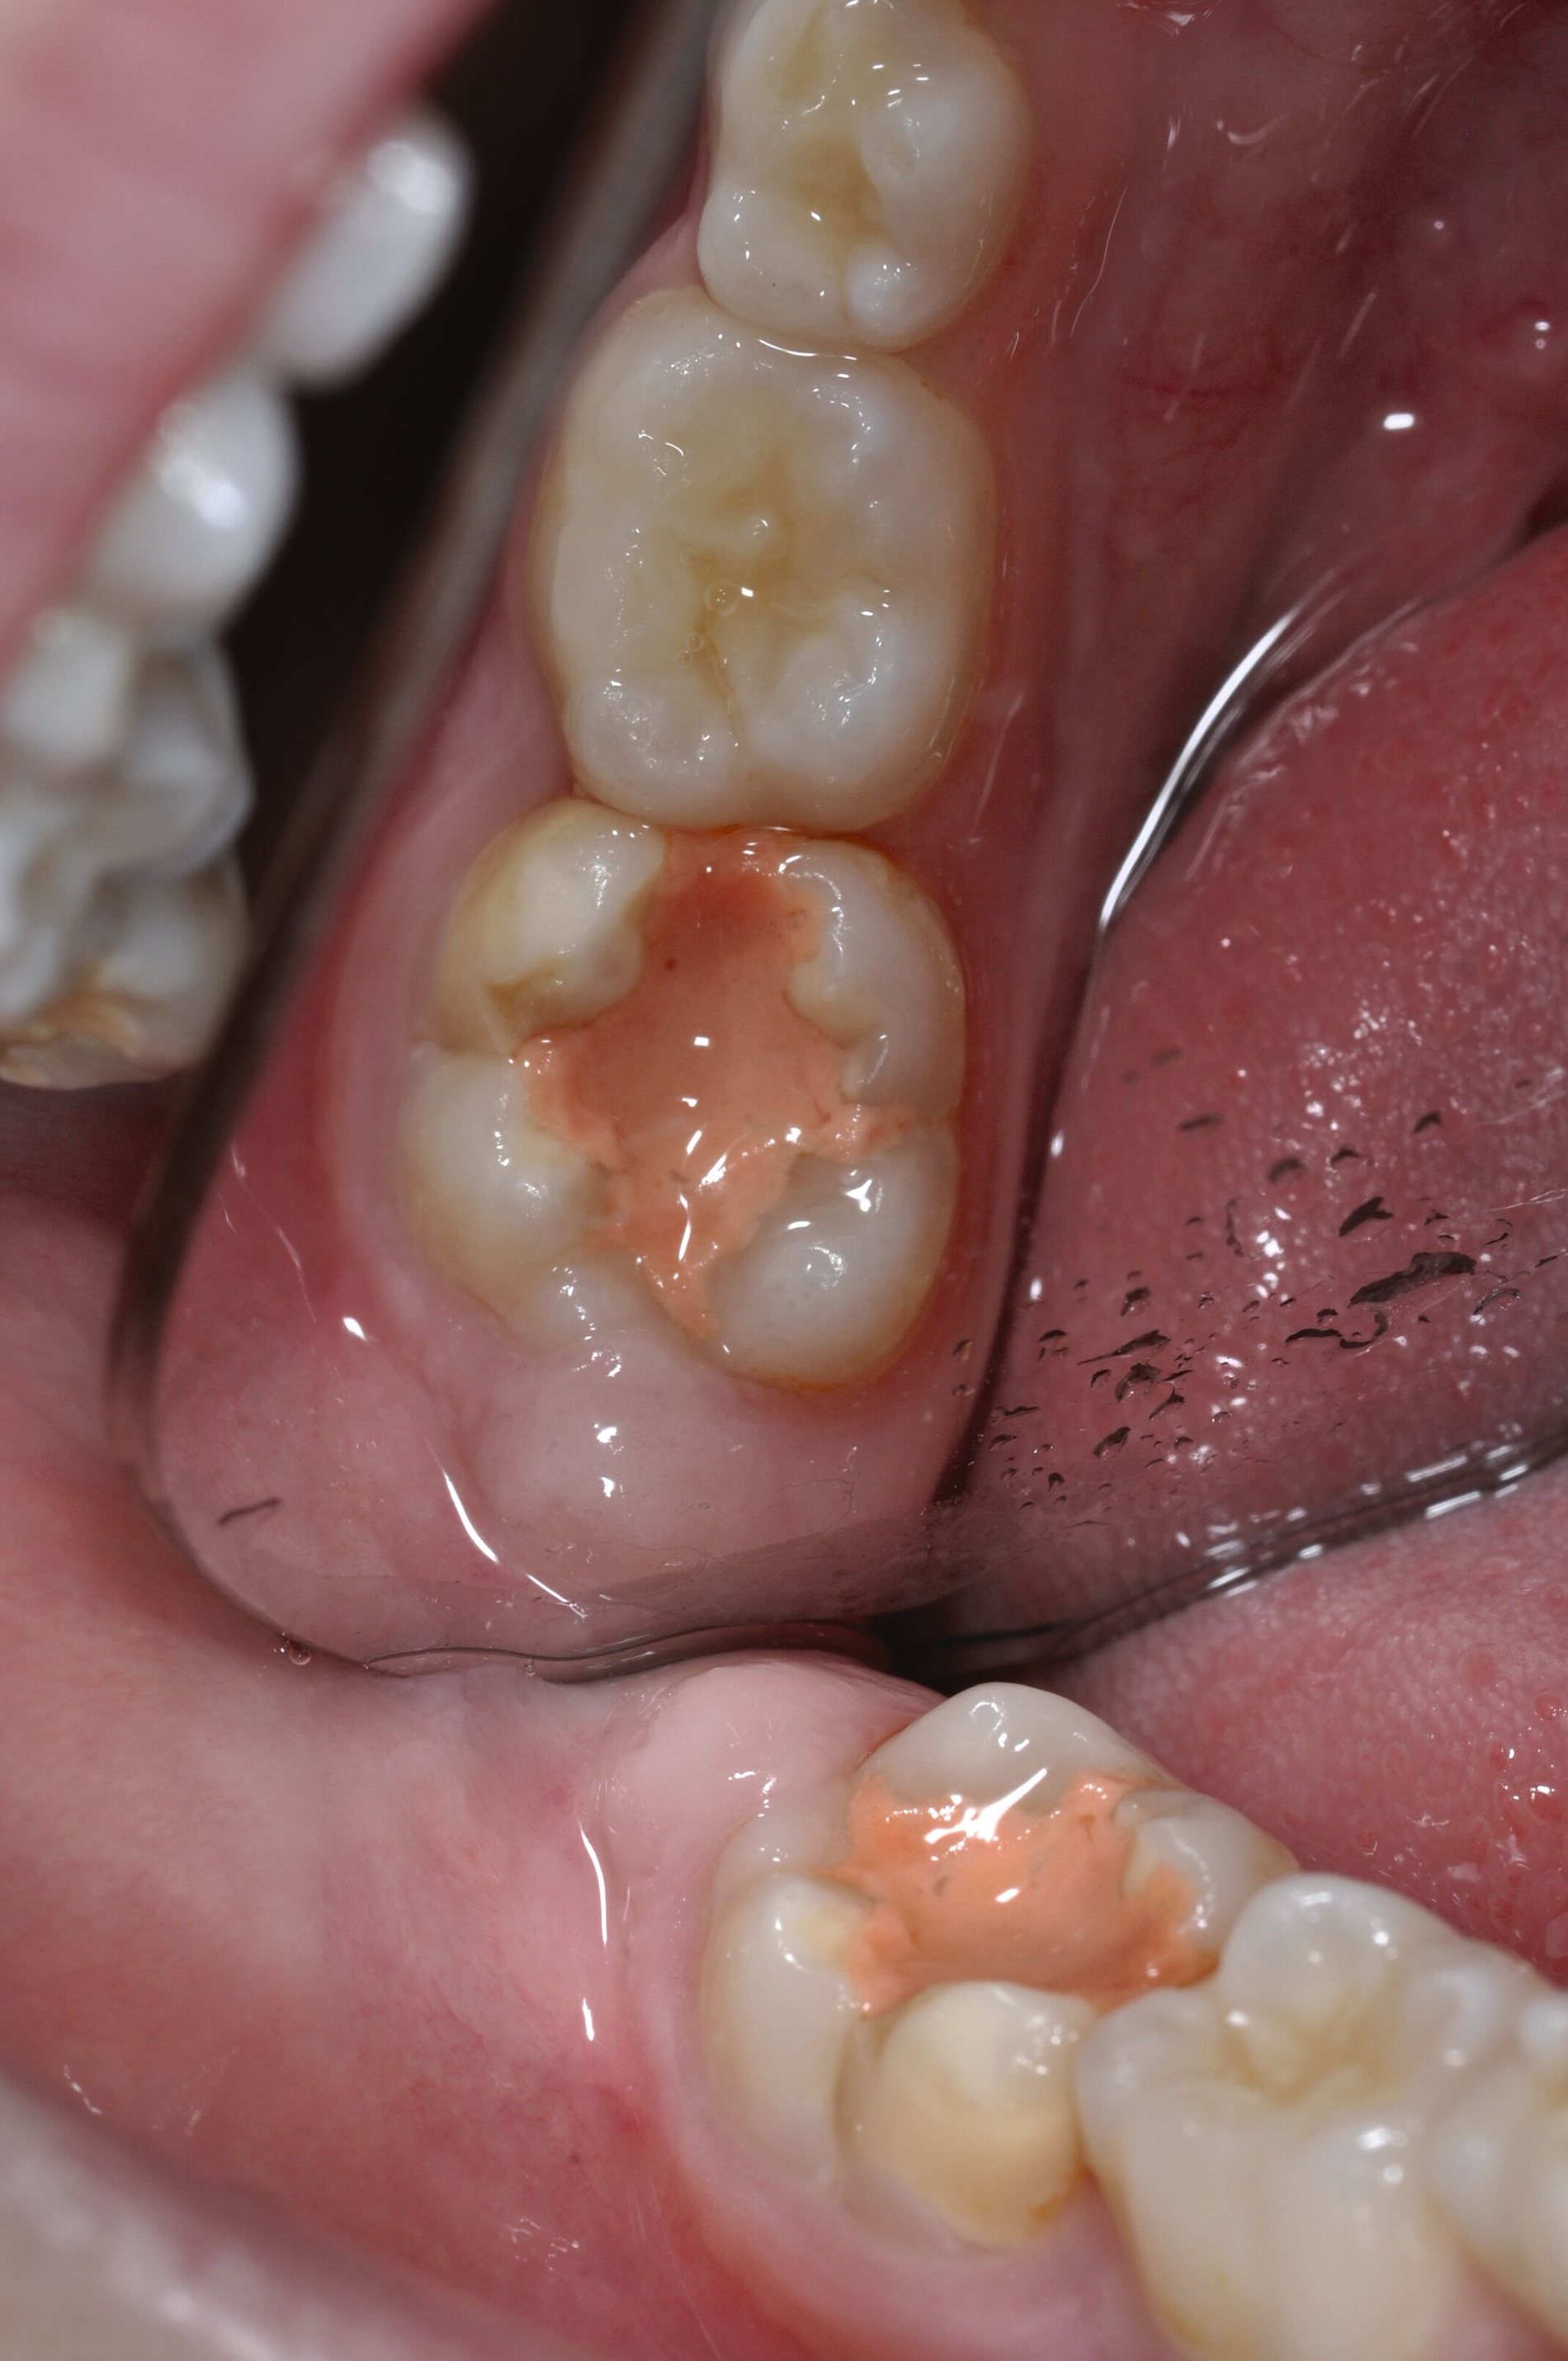

Der Vorteil der Methode ist, dass die betroffenen Zähne auch ohne Lokalanästhesie und Präparation versorgt werden können. Die temporäre Versorgung ermöglicht es, die Patienten an die zahnärztliche Behandlung zu gewöhnen. Häufig führt diese temporäre Versorgung auch zu einer Reduktion der Hypersensitivität der MIH-Zähne. Nachteil der GIZ-Versorgung ist das Risiko einer Füllungsfraktur oder eines vollständigen Verlusts der Füllung (Abbildung 4). Aktuelle Erhebungen bestätigen eine Erfolgsrate von über 80 Prozent nach einem bis zwei Jahren [Durmus et al., 2021; Mahfouz et al., 2025].

Der Behandlungsfall (Abbildung 4d) veranschaulicht die Schwächen des Verfahrens. Wird das Angebot der regelmäßigen Kontrollen nicht wahrgenommen, so droht bei Verlust der Füllung die Kariesprogression. In dem vorliegenden Fall konnte jedoch eine endodontische Maßnahme vermieden und durch die selektive Kariesentfernung die Zahnhartsubstanz weitestgehend erhalten werden.